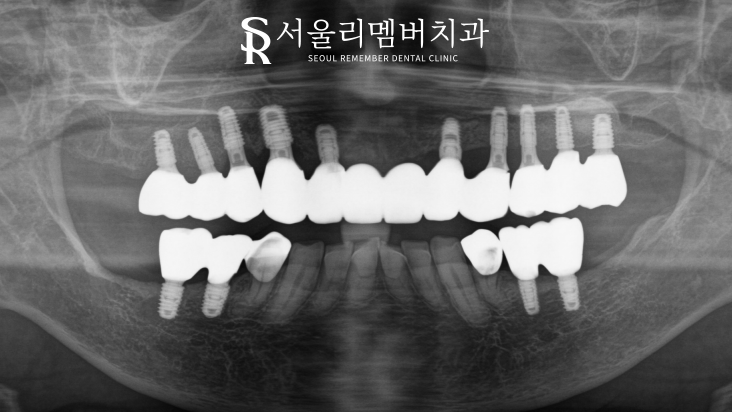

파노라마 사진을 먼저 확인해 보면

올바른 교합, 맞물림으로 위치를 잡고 있는

고정체와 보철을 볼 수 있습니다.

골이식을 동반해서 그런지

훨씬 안정적인 유지를 얻고 있네요.